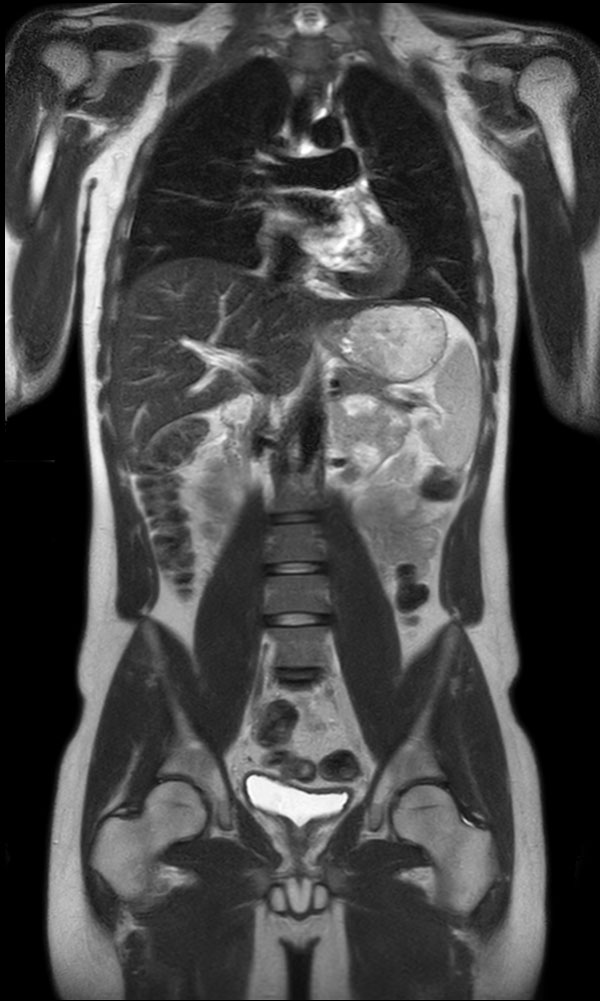

Total torso and liver

• Clinical Application